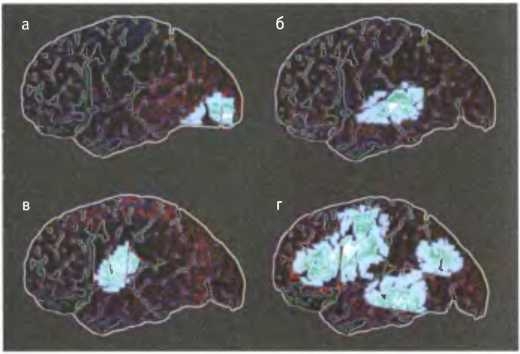

а) Чтение сопровождается возбуждением зрительной коры.

б) Восприятие речи на слух сопровождается возбуждением слуховой коры,

в) Обдумывание слов сопровождается возбуждением зоны Брока — центра артикуляции,

г) Обдумывание слов и их произнесение сопровождается активностью многих областей мозга.